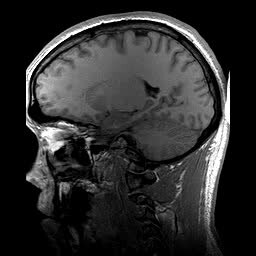

T1-weighted MRI sagittal slice.Week 03. Structural MRI & Contrast

T1, T2, and T2* relaxation. Tissue properties, pulse sequences, and understanding structural brain anatomy in 3D.